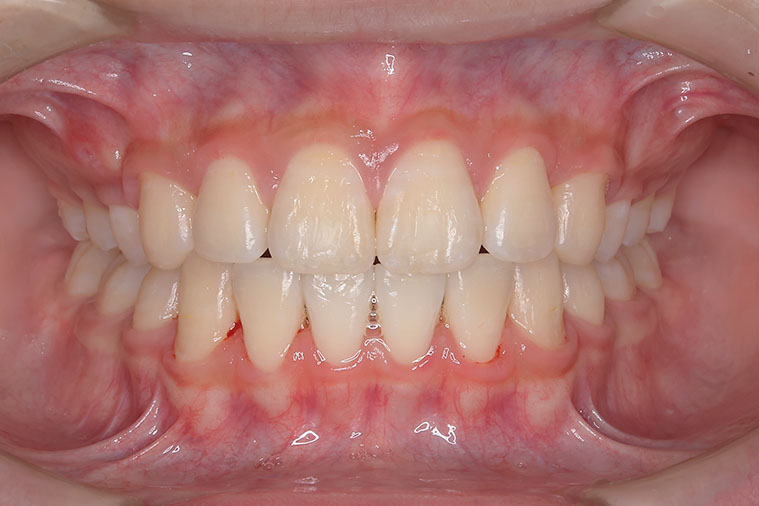

歯が重なっている、出っ歯を治したい 以前に治療した方からの紹介で来院した患者さんです。 上下顎前歯部の叢生(がたつき)、上下顎前歯の前方傾斜、 骨格的上顎前突傾向でした。 小児矯正で叢生の緩和を行い、 本格矯正で前方傾斜した前歯の改善を行いました。 マルチブラケット 動的治療期間 3年3か月 調整回数25回